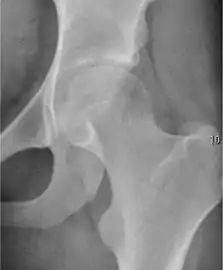

Radiological signs of transient osteoporosis of the hip include localized osteoporosis of the femoral head and neck (Figure 8). Nevertheless, final diagnosis has to be made with MRI to differentiate it from avascular necrosis and from insufficiency or stress fractures of the femoral head or neck. In case of AVN, radiographs can only demonstrate delayed or advanced signs. Staging according to Ficat classification ranges between normal appearance (stage I), slight increased density in the femoral head (stage II), subchondral collapse of the femoral head with or without “crescent” sign (stage III), and advanced collapse with secondary osteoarthritis (stage IV). In the case of stress or insufficiency fractures X-ray sensitivity has been proven to be much lower than MRI, which is currently the gold standard.[1]

X-ray of a patient with transient osteoporosis of the left hip showing osteoporosis.[1]